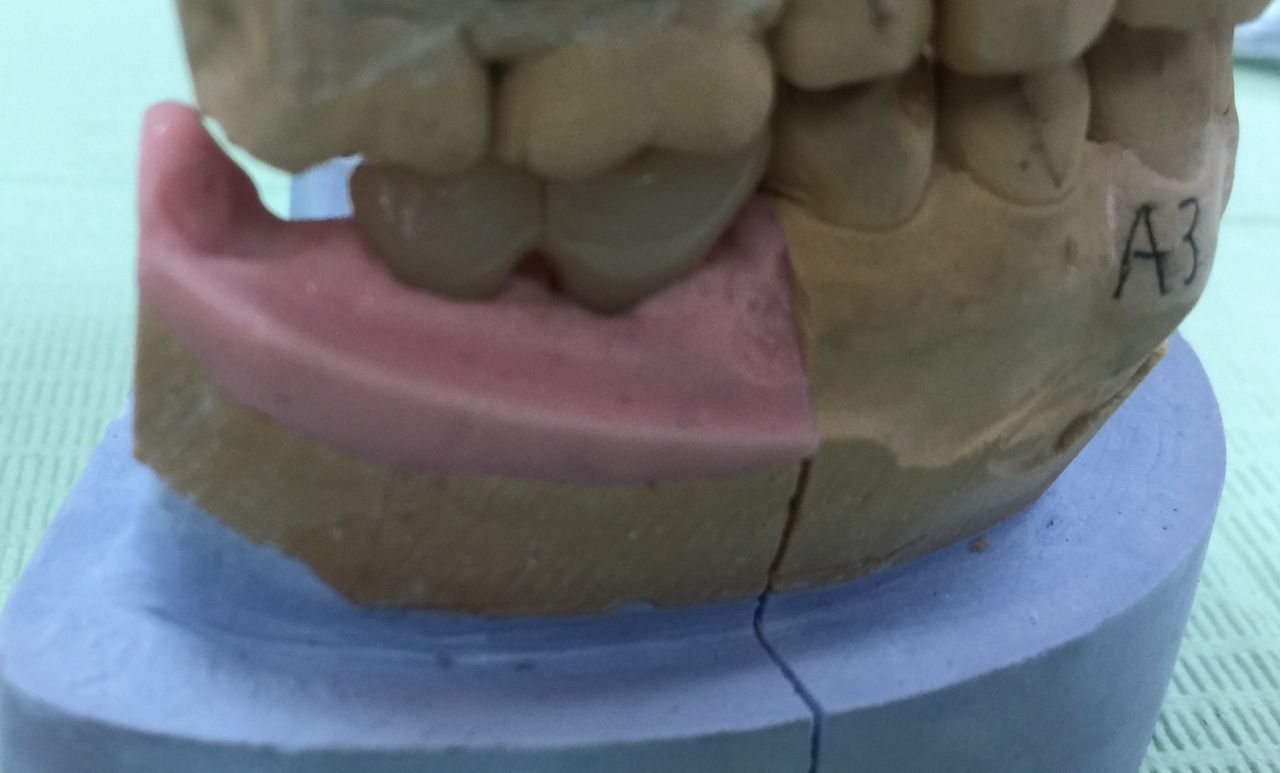

技工士さんが、コレをもとに全てがセラミックでできた被せ物を作ってくれます。

これをネジを使ってインプラントに接続します。